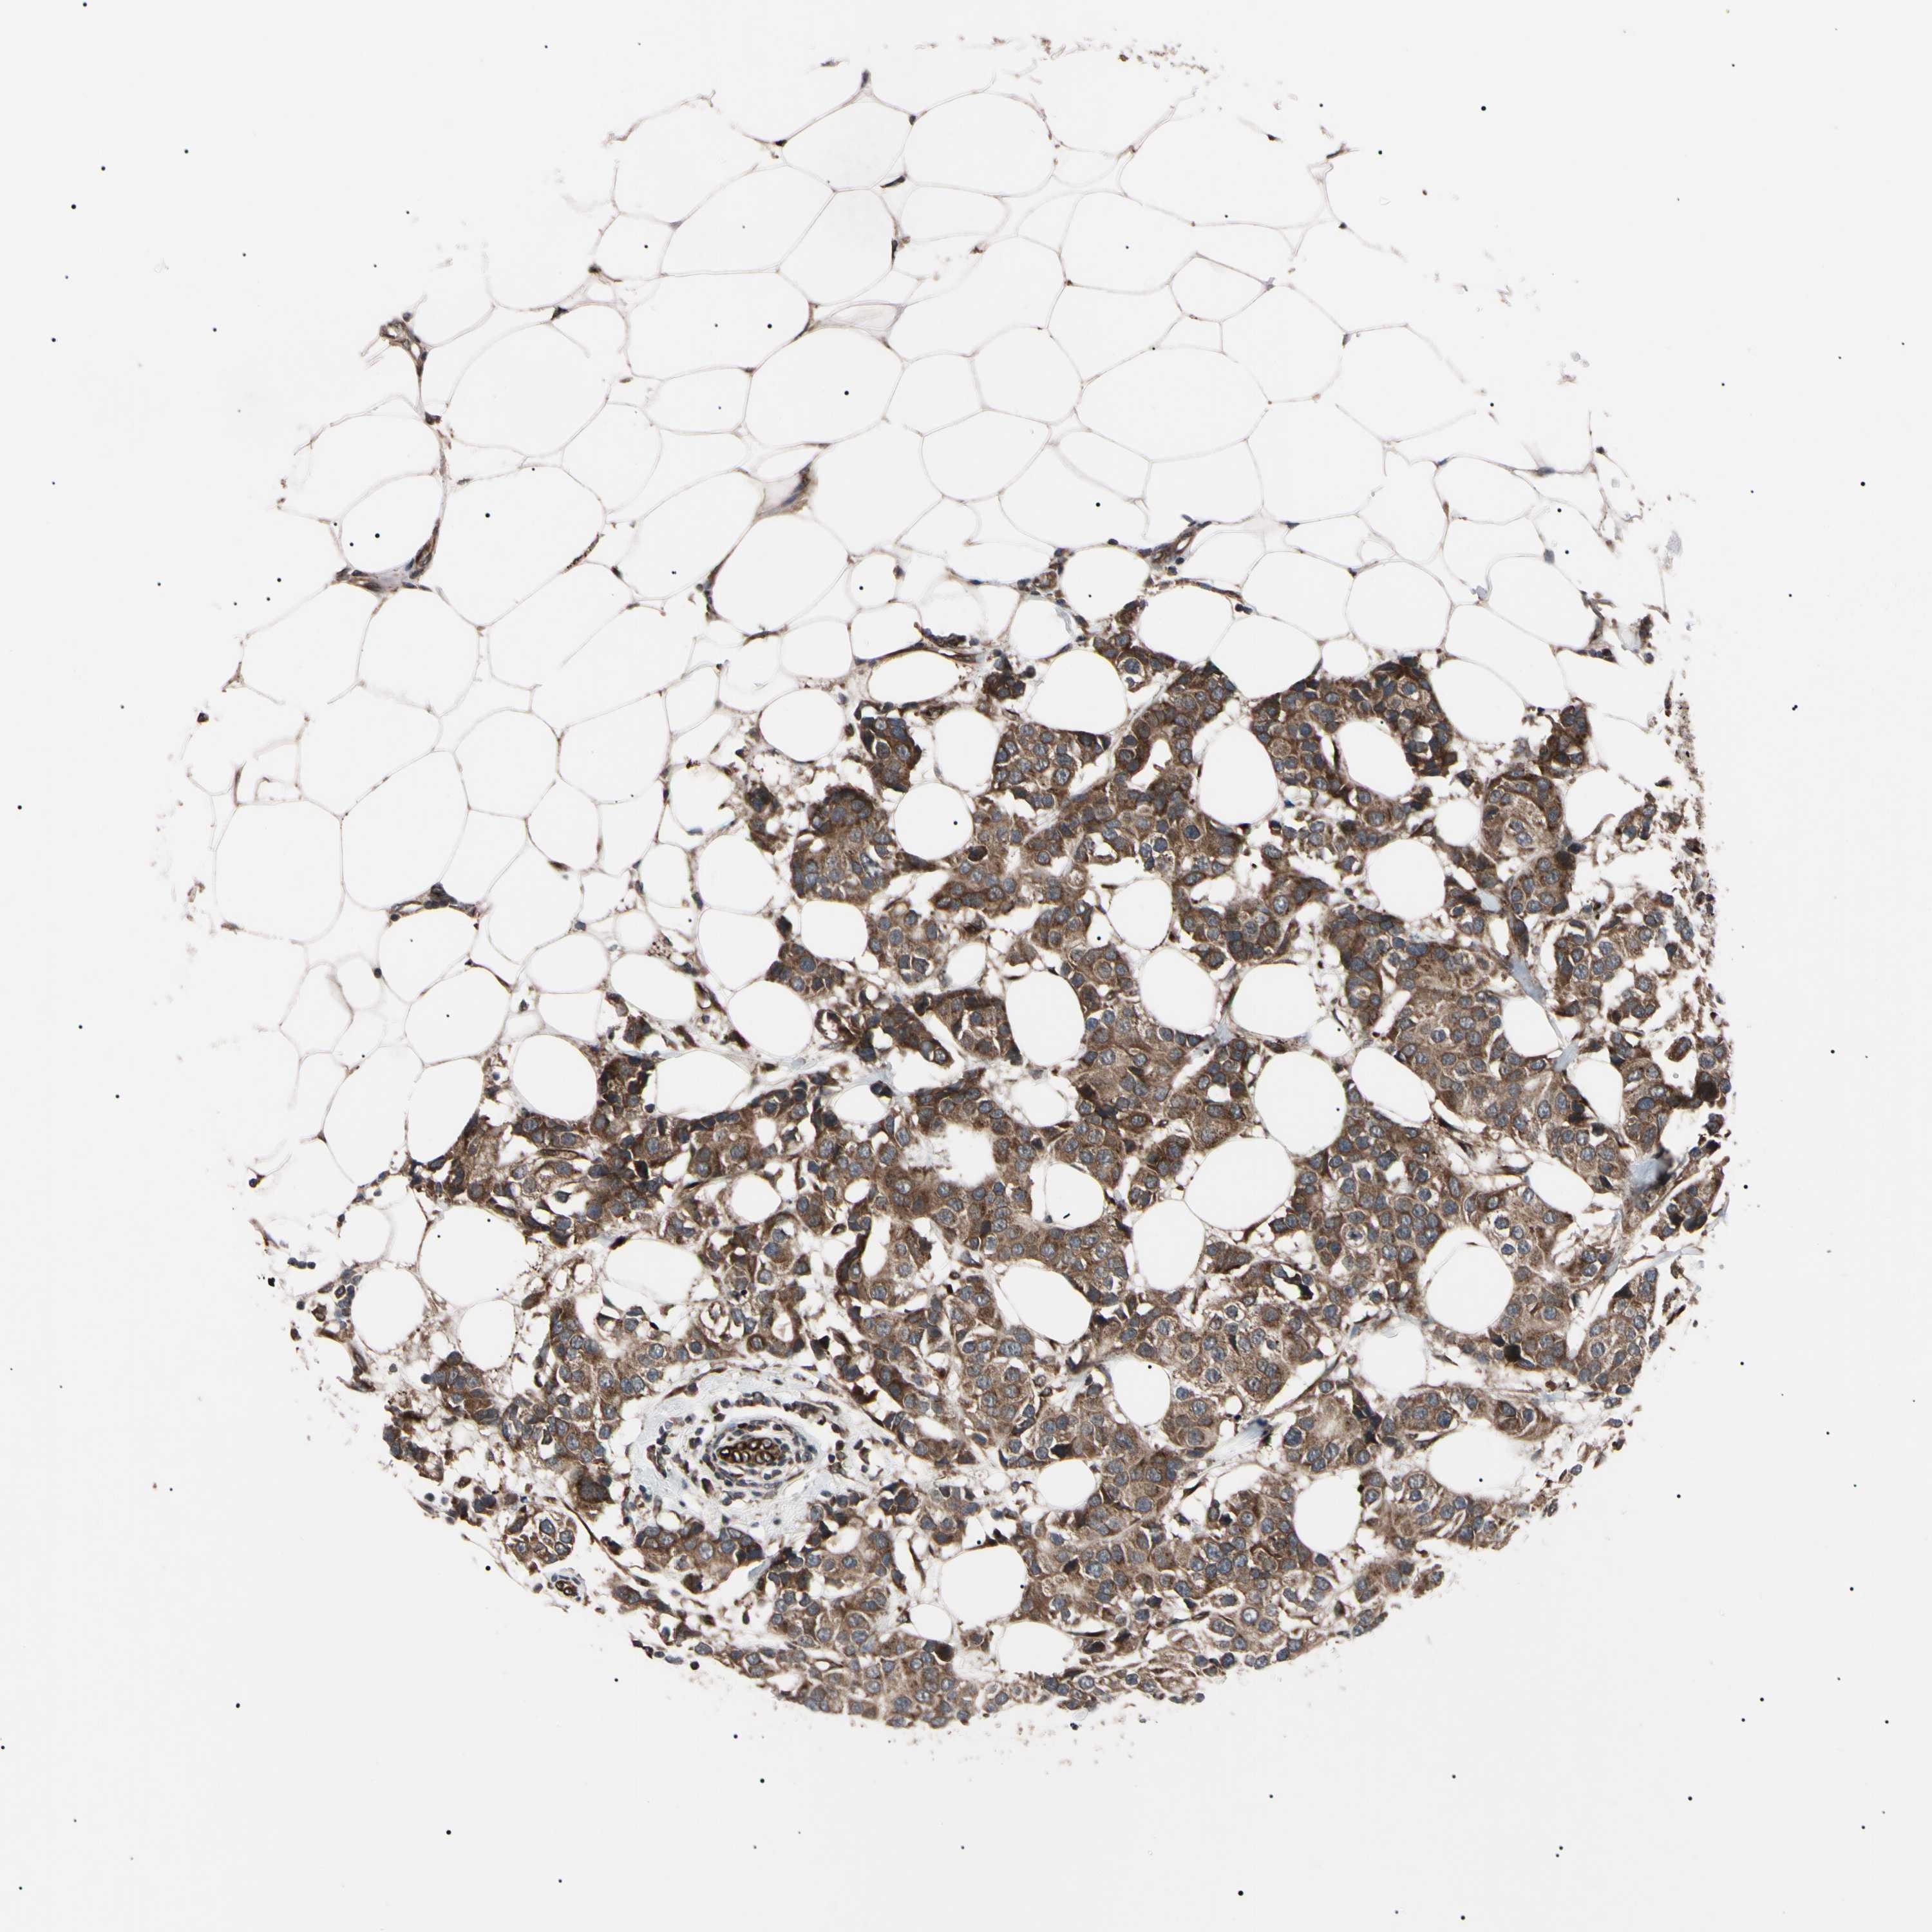

BRCA TCGA BRCA VALIDATION PROTEIN EXPRESSION